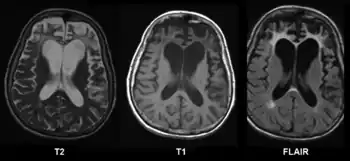

CT and MRI are most commonly used to observe the brain for cerebral atrophy. A CT scan takes cross sectional images of the brain using X-rays, while an MRI uses a magnetic field. With both measures, multiple images can be compared to see if there is a loss in brain volume over time.[19]

Cerebral atrophy can be hard to distinguish from hydrocephalus because both cerebral atrophy and hydrocephalus involve an increase in cerebrospinal fluid (CSF) volume. In cerebral atrophy, this increase in CSF volume comes as a result of the decrease in cortical volume. In hydrocephalus, the increase in volume happens due to the CSF itself.[19]